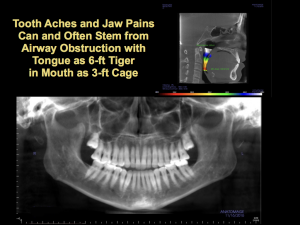

airway obstruction

BK’s anterior open bite came from having a normal size-6 tongue inside a size-3 mouth, which drives the tongue into the oral airway and creates a wide range of medical, dental, and mental symptoms that I call Impaired Mouth Syndrome.

Cephalometric analysis showed that BK had an undiagnosed class III malocclusion, with retruded maxilla and entrapped mandible, which combined to give her neck and shoulder pain. CBCT imaging showed BK’s airway was 30-50% from low normal and that her cervical spinal segments were misaligned.

In my opinion, the mouth has a central role in whole body health, but the mouth is left off nearly all the medical and dental treatment plans today. That is why I wrote my book Six-foot Tiger Three-foot Cage (6T3C): to introduce these concepts and practices that impact over 90% of patients and their dentists, doctors, and therapists.